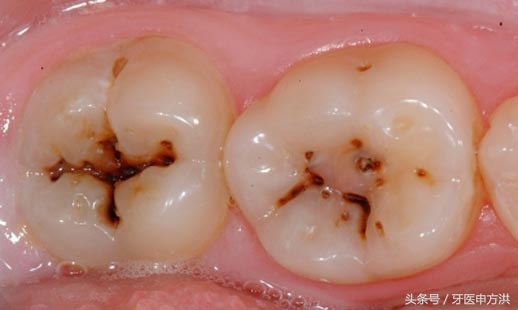

看得见的一般是静止龋或慢性龋,通常呈黑褐色,质地较干硬,这种龋坏的速度比较慢,属于慢工出细活的类型。

看不见的就是急性龋,多见于儿童和青年人。通常呈白色或者米黄色,质地湿软,这种龋坏速度异常快,没一会功夫就能把你的牙齿钻个底朝天。